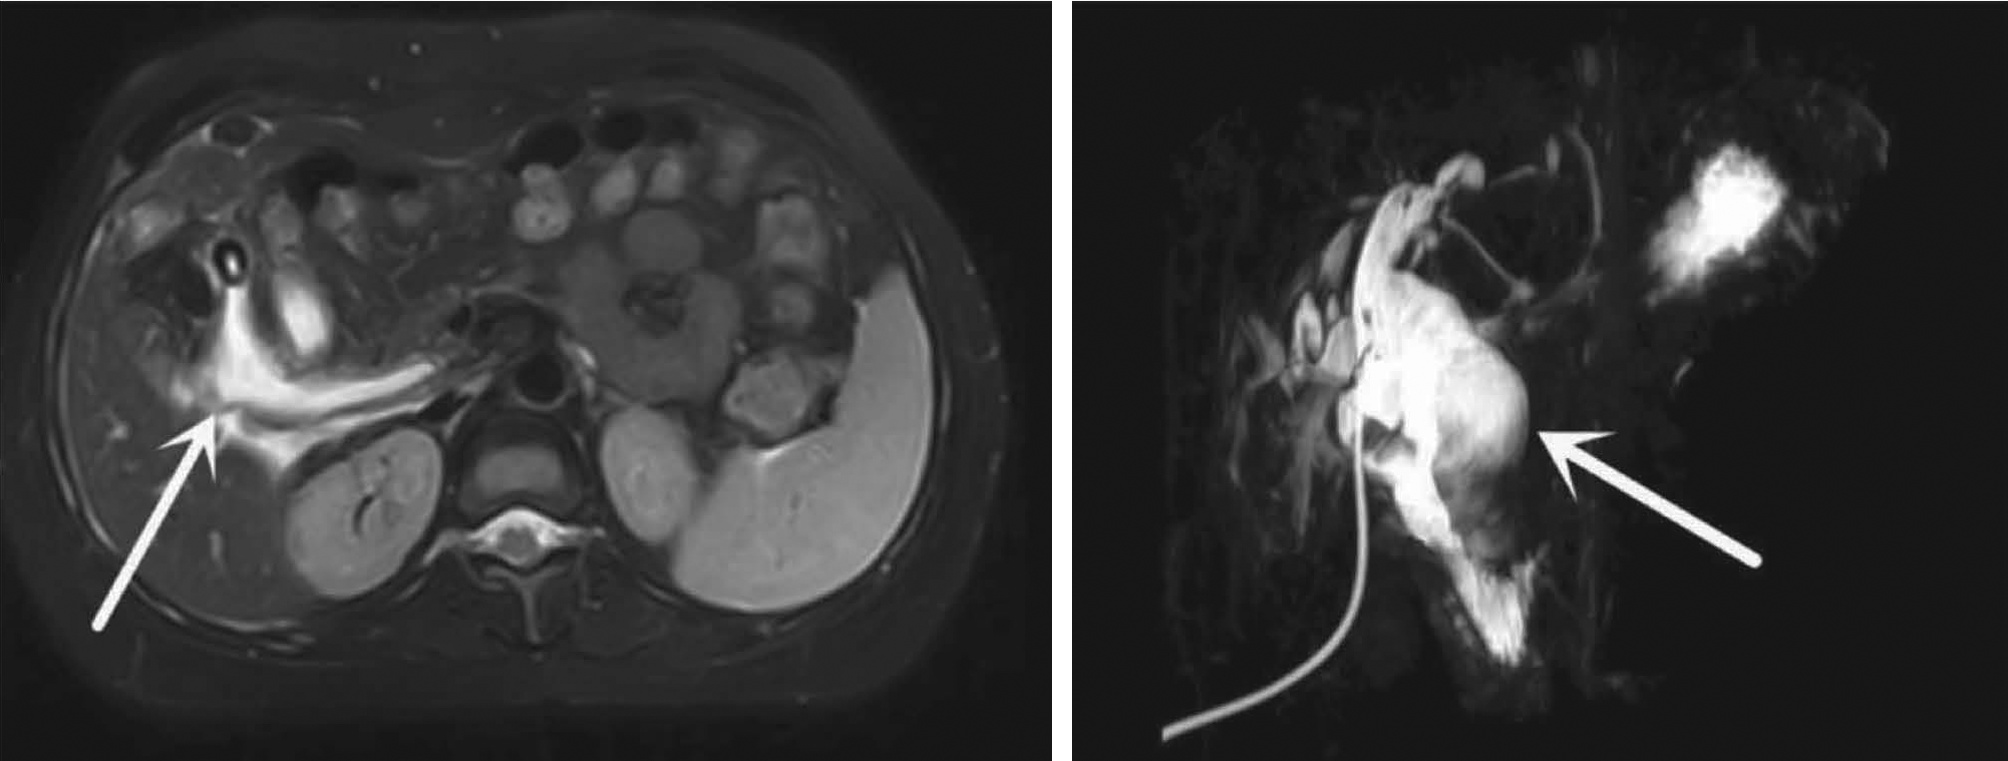

目的  评价在慢性乙型肝炎患者腹部CT中通过测量胸、腰椎CT值,诊断骨量减少/骨质疏松的诊断价值。分析慢性乙型肝炎患者发生骨量减少/骨质疏松的危险因素。  方法  回顾性纳入2019年1月—2020年12月在昆明医科大学第二附属医院就诊的慢性乙型肝炎患者112例,所有患者均完善了腹部CT检查,部分患者完善了双能X线骨密度测定(DXA)。测量T12椎体至L3椎体的CT值,分析每一椎体CT值与DXA检查基于L1~L4椎体测得的T-score值相比诊断骨量减少/骨质疏松的诊断价值。以椎体CT值为诊断标准,将纳入的慢性乙型肝炎患者分为骨量减少/骨质疏松组(n=55)与骨量正常组(n=57),对比两组患者临床特征、生化指标,分析慢性乙型肝炎患者发生骨量减少/骨质疏松的危险因素。符合正态分布的计量资料两组间比较采用t检验;非正态分布的计量资料两组间比较采用Mann-Whitney U检验。计数资料组间比较采用χ2检验、Fisher确切检验、Bonferroni校正检验。相关性采用Pearson相关分析。多因素分析采用二元logistic回归分析。根据受试者工作特征曲线(ROC曲线)评估T12~L3椎体CT值诊断慢性乙型肝炎患者合并骨量减少/骨质疏松的诊断价值。一致性检验采用Kappa检验。  结果  分析46例在同次住院中完善了腹部CT和DXA检查患者的T12~L3椎体CT值,均分别与DXA检查结果中基于L1~L4椎体计算的T-score值有显著正相关性(rT12=0.694,rL1=0.661,rL2=0.781,rL3=0.685,P值均<0.001);经ROC曲线分析,L2椎体CT值ROC曲线下面积最大(0.863),诊断骨量减少/骨质疏松具有较好准确性,与DXA检查结果具有较好一致性(K=0.648,P<0.001)。分析112例慢性乙型肝炎患者临床特征、生化指标,提示高龄(比值比为1.108,95%CI:1.026~1.196,P=0.009)、合并肌少症(比值比为2.788,95%CI:1.009~7.707,P=0.048) 是骨量减少/骨质疏松发生的危险因素。  结论  慢性乙型肝炎患者常需定期复查腹部CT评估肝脏疾病进展情况,通过测量患者腹部CT图像中L2椎体CT值、L3椎体层面骨骼肌面积筛查是否存在骨量减少/骨质疏松、肌少症,及时干预,提高患者的预后、生活质量,具有较高临床意义。